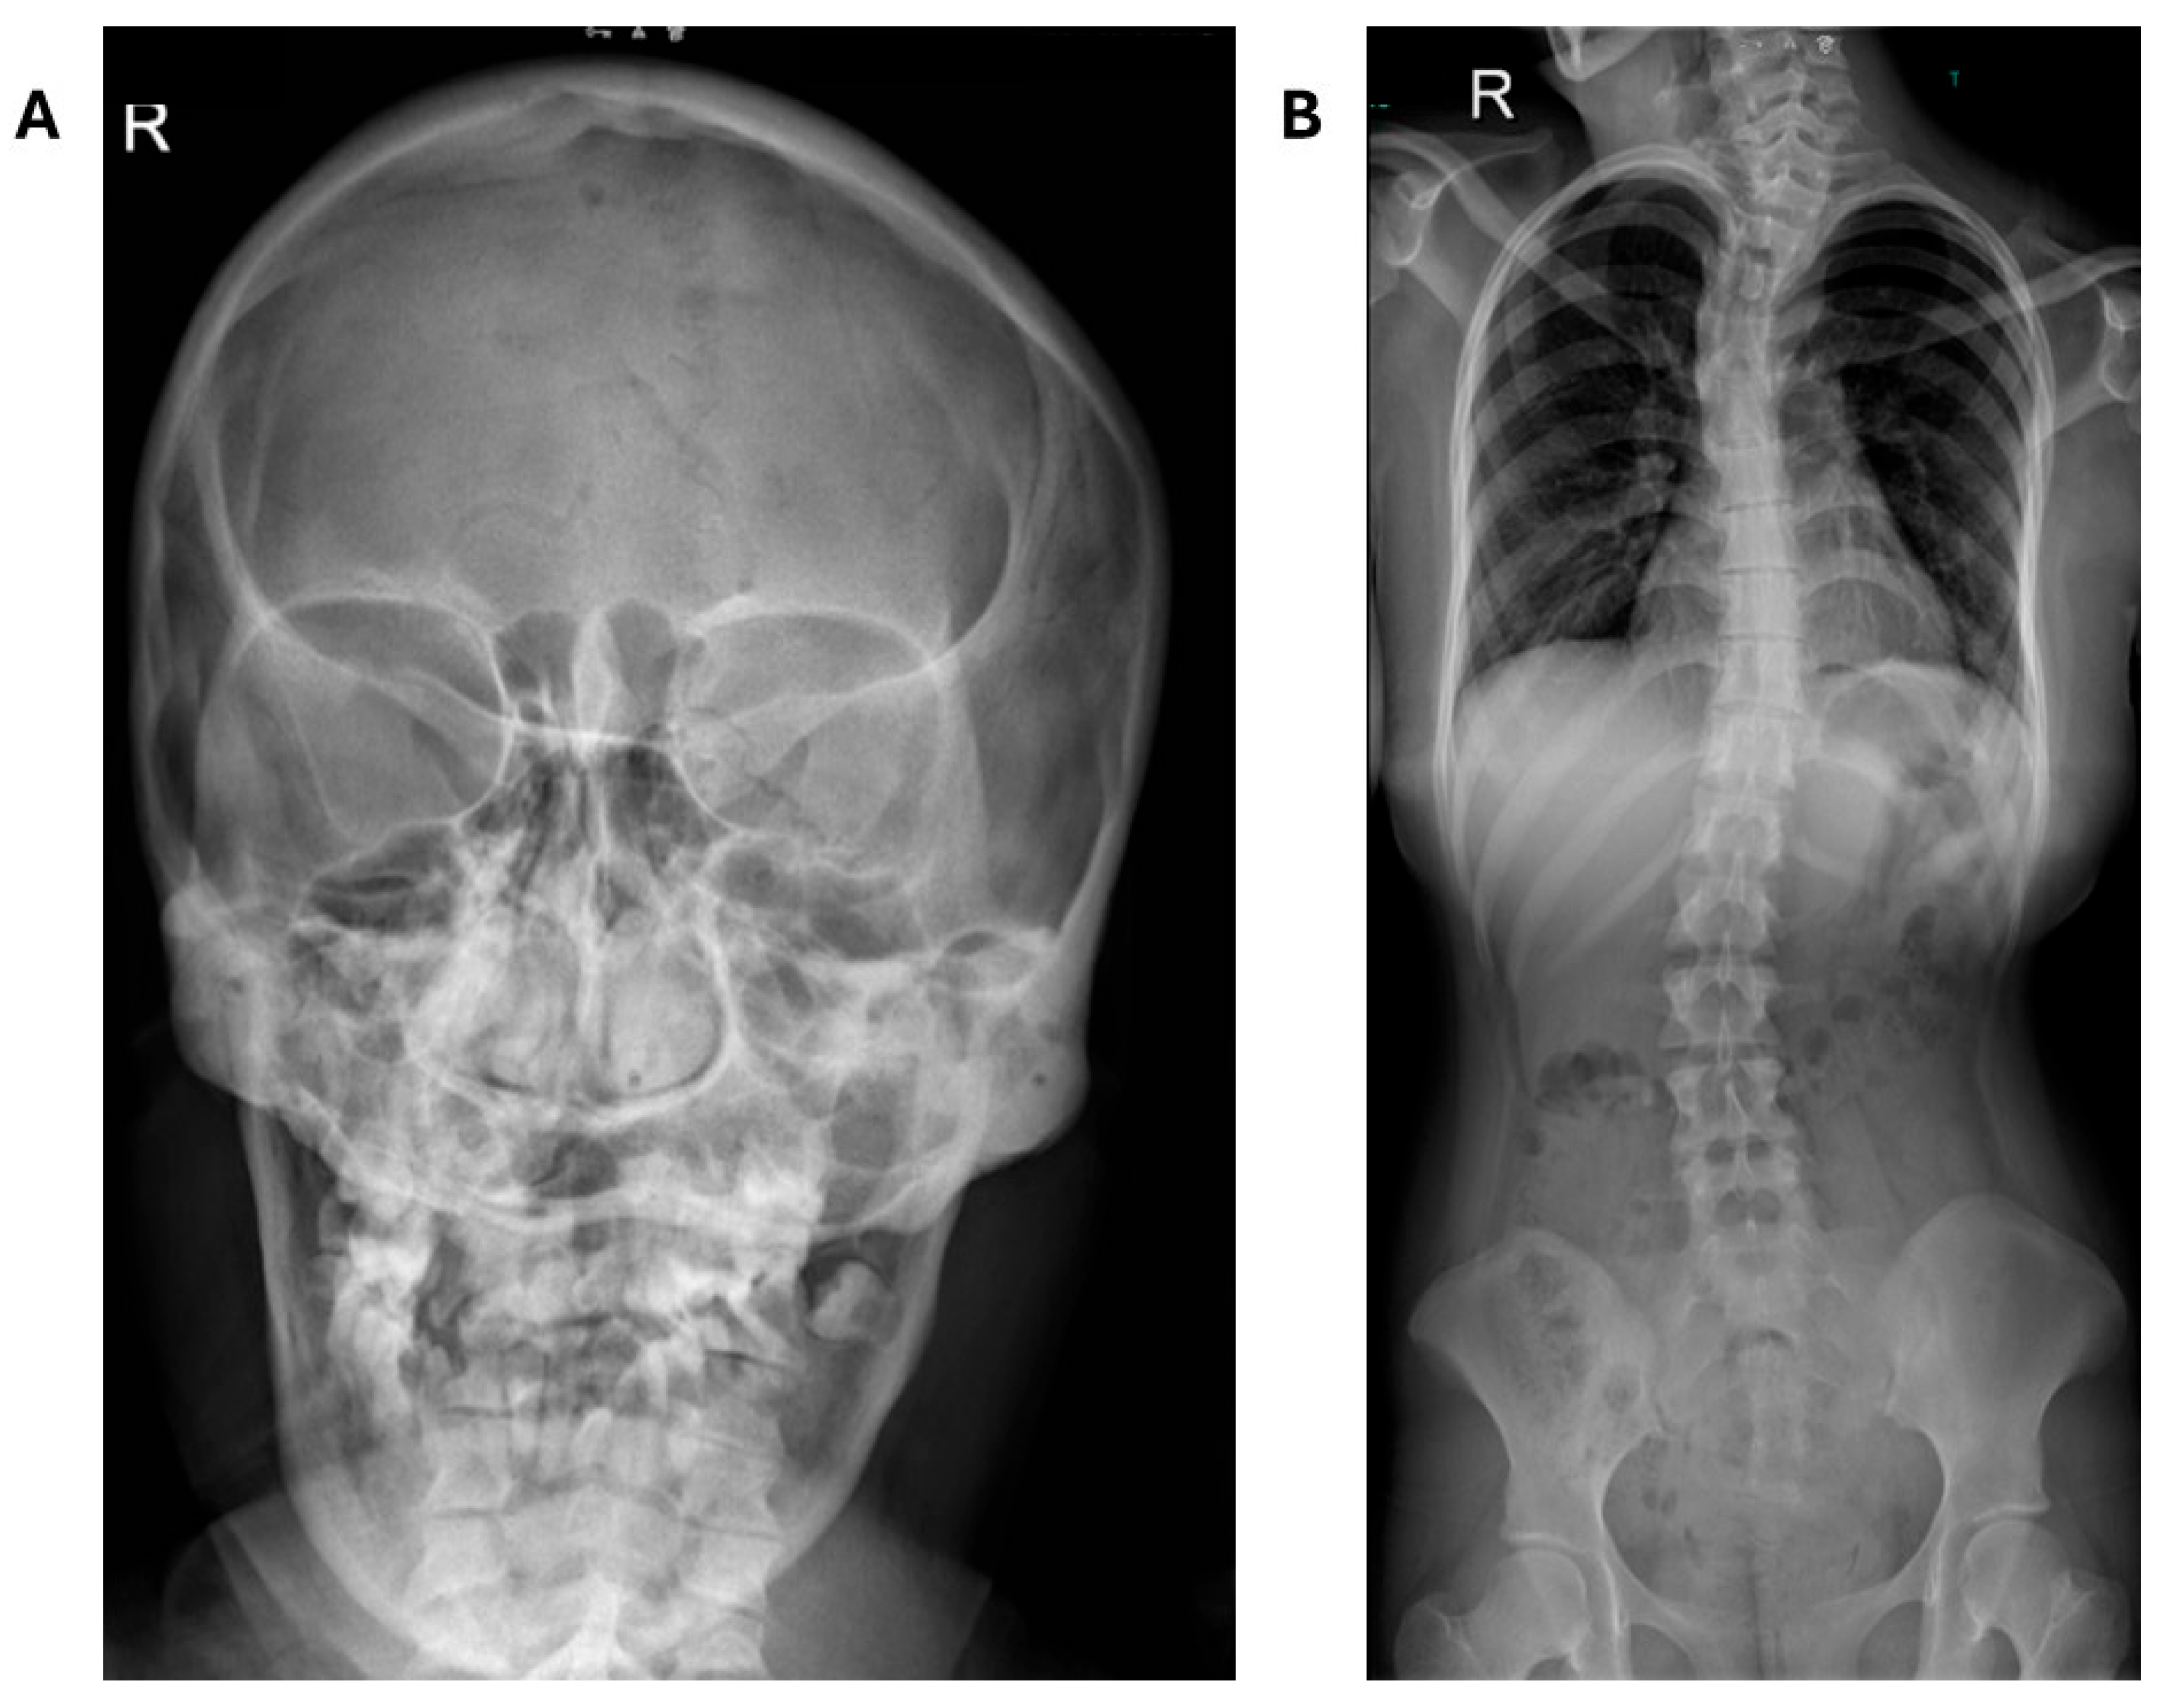

| SBBYS-type Ohdo syndrome | KAT6B | Intellectual disability, blepharophimosis, ptosis, long thumbs, dental anomalies | Hallux valgus, scoliosis, normal patellae, shortened phalanges, ulnar variance |